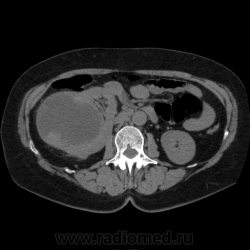

Солитарное кистовидное образование правой почки с неравномерно утолщенными стенками, у узлами в капсуле, накапливающими контраст. Фасция Гарота справа тяжистая. По классификации - киста 4-й категории, крайне велика возможность малигнезации. Может, показалось вовлечение парааортальных лимфоузлов?

В 1986 г. M.A. Bosniak создал “рабочую” классификацию кистовидных образований почек, которая позволяет предположить доброкачественность или злокачественность кистозных образований при распределении их по радиологическим критериям на 4 основные категории. Образования I и II категорий являются заведомо доброкачественными и поэтому нуждаются в динамическом наблюдении или, по показаниям, в лечебной пункции со склеротерапией под контролем УЗИ или КТ. Образования III категории могут быть как доброкачественными, так и злокачественными, а образования IV категории – кистозные почечноклеточные раки.

Третья категория – более сложные кистовидные образования, которые демонстрируют какие-либо радиологические признаки злокачественности. Некоторые из этих образований оказываются доброкачественными (например, сложные кисты, мультилокулярная кистозная нефрома, геморрагические кисты), другие злокачественными (почечные кистозно-клеточные карциномы). Одним из критериев, которые заставляютотнести кистовидное образование почки к III категории, является повышение плотности ее стенки. При КТ у кистовидного образования выявляется плотная (вплоть до обызвествления) стенка по всему периметру кисты, хотя образование может сохранять некоторые признаки простой кисты почки. Следующим критерием является характер отложения кальцинатов. Если при КТ в образовании определяется большое количество кальцинатов, расположенных глыбками (как на периферии образования, так и в центре), если из-за этого стенки и перегородки становятся утолщенными, неправильной формы, то данное образование следует отнести к III категории. Наличие множественных перегородок толщиной более 1 мм, видимых утолщений в месте прикрепления перегородок к стенкам кисты позволяет также отнести данное образование к третьей категории. Большое количество тонких перегородок в образовании определяет его как сложную кисту. Такие образования крайне сложно дифференцировать как доброкачественные или злокачественные, но они чаще по КТ-картине выглядят как злокачественные. При КТ определяется негомогенное многокамерное образование округлой или неправильной округлой формы, возможно с капсулой. Плотность образования неоднородная, пониженная относительно паренхимы, в полости образования видно большое количество перегородок.

IV категория – поражения явно злокачественные, обычно кистозные почечно-клеточные карциномы. Основными симптомами кистозной опухоли при КТ являются: неправильная форма кисты, негомогенность структуры образования с участками некроза, деформация почки, нечеткая граница между кистой и паренхимой почки, плотностные показатели могут быть выше, чем в кистах (+20…+40 Н), т.е. близкие к плотности почечной паренхимы. Капсула имеет неравномерную толщину, часто обызвествлена по периферии. Возможна визуализация дополнительных фокусов образования (кажущееся увеличение образования в размерах и изменение его конфигурации) после введения контрастного вещества. Но самым важным симптомом является увеличение плотности внутреннего содержимого после внутривенного введения контрастного вещества. Часто на серии срезов удается выявить эндофитные гребневидные фестончатые разрастания, выступающие в просвет кистозной полости. Особенно хорошо этот мягкотканый васкуляризированный компонент опухоли проявляется при внутривенном контрастировании

Всё верно, я тоже пользуюсь данной классификацией по Босняку, кистозно-солидное образование правой почки я отнёс к 4 категории, нужно отметить, что преобладает кистозный компонент, но солидный компонент довольно приличный и значительно накапливает контрастное вещество до 80-90HU, четко капсулу образования не отграничить. Ко всему этому в паренхиматозную фазу четко дифференцируются единичные парааортальные и паракавалльные л/узлы. С большей степенью вероятности в данном случае cr почки. Пациентка на следующей неделе будет госпитализирована для верификации.

Описание изменений, выявленных при микроскопическом исследовании: опухоль представлена крупными альвеолярными структурами из светлых, оптически пустых клеток с мелкими гиперхромными ядрами, опухоль частично инфильтрирует капсулу почки, полностью прорастает стенку почечной лоханки, образуя полиповидные структуры. Одиночные опухолевые эмболы в сосудах почки. Отдельно присланный узел представлен тканью почки с опухолевым узлом, строение которого соответствует выше описанной опухоли. В воротах почки патологических образований не найдено. Во всех исследованных лимфоузлах (6 шт.) метастазы опухоли с замещением всей ткани лимфоузлов.

Патоморфологическое заключение: массивный светлоклеточный почечно-клеточный рак почки с частичной инфильтрацией капсулы, прорастанием в ЧЛС, опухолевыми эмболами в сосудах, множественными метастазами в забрюшинные лимфоузлы (6 шт